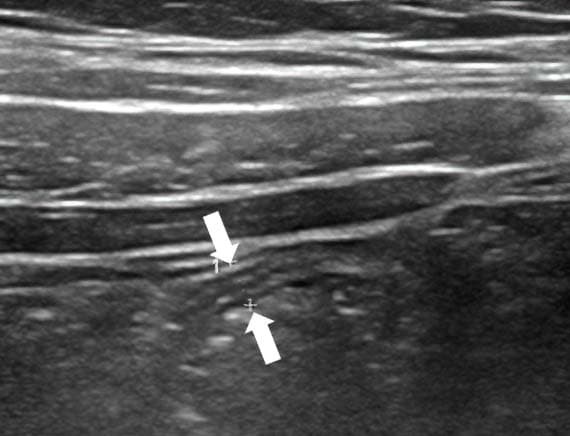

Обнаружение увеличенных лимфоузлов (более 5 мм в поперечнике) по ходу корня брыжейки тонкой кишки является вторичным признаком воспаления в илеоцекальной области при остром аппендиците (см. рис. 14). Этот признак неспецифичен для острого аппендицита, поскольку лимфаденопатия в брюшной полости может быть как при аппендиците, так и без него, являясь частой реакцией на воспалительные заболевания толстого и тонкого кишечника, а также может отмечаться при первичном мезадените. Увеличенные лимфоузлы имеют вид гипоэхогенных овальных структур, несжимаемых при компрессии.

Рисунок 14. Увеличенный лимфоузел.